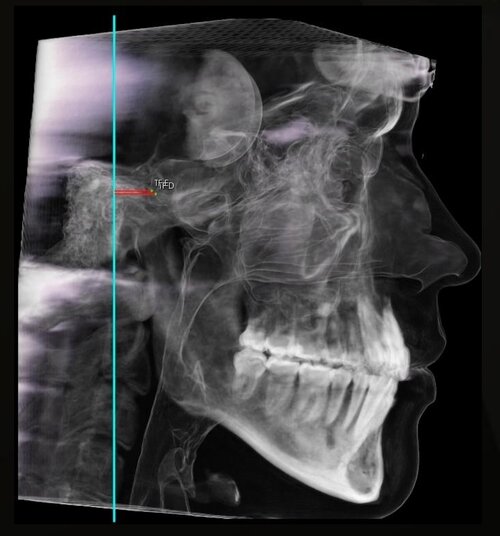

i have compressed airway (84mm smallest width), but doctors said i don't need surgery because i dont have sleep apnea.

also, they don't want to expand my palate because they said its only a little bit narrow so no worth the risk (upper palate 38.5mm, lower palate 42mm).

they want to extract my wisdom teeth to create space, and they said my overbite is gonna get fixed when they align my upper teeth, because they are blocking my lower jaw (my upper teeth grew inwards).